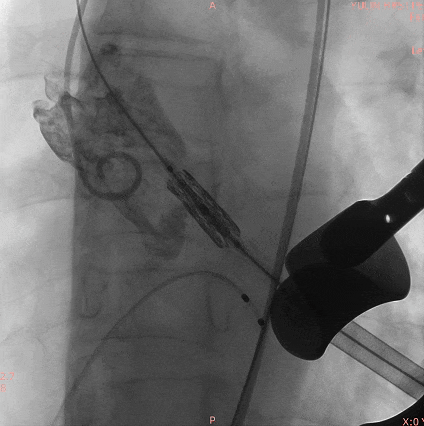

25#Renatus瓣膜造影定位

快速起搏下5atm精准球扩释放25#Renatus瓣膜